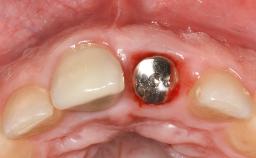

Treatment of Peri-Implant Mucositis at a Zirconia Implant

Frank Schwarz, Ausra Ramanauskaite

Recent clinical studies, most with short-to-medium term observation periods, have reported on the favorable clinical performance of zirconia implants in terms of survival rates, clinical, and radiographic outcomes (Roehling and coworkers 2016; Roehling and coworkers 2017; Rodriguez and coworkers 2018; Lorenz and coworkers 2019). Nonetheless, a rather high incidence of peri-implant disease at zirconia implants (39% of implants) was noted throughout a two-year period, highlighting the need for treatment protocols of peri-implant diseases at zirconia implants (Becker and coworkers 2017).